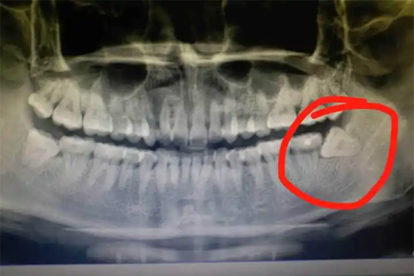

对于无症状且位置正常的智齿,可定期口腔检查观察。通过全景片评估智齿与邻牙关系,每6-12个月复查一次。若出现萌出方向偏移或邻牙牙根吸收迹象需及时干预。

阻生智齿或反复发炎的智齿建议手术拔除。水平阻生需去骨分牙,近中阻生采用涡轮机分割牙冠。术后24小时内冰敷减轻肿胀,72小时后开始温热含漱促进愈合。